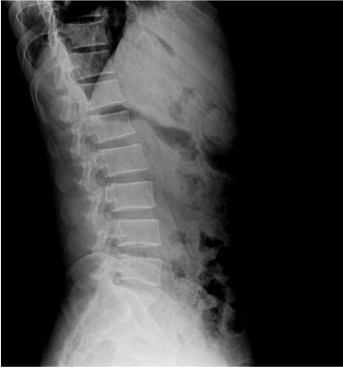

臨床圖片

微信圖片_20210927001059